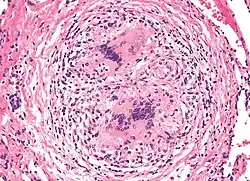

In den Lungen und den angrenzenden Lymphknoten werden epitheloidzellige Granulome ausgebildet. Selten finden sich durch Beryllium induzierte Granulome auch in der Milz, Leber und Nebenniere. Im weiteren Verlauf kommt es zu einer Fibrose der granulomatösen Veränderungen.

Der Verdacht auf eine Berylliose ergibt sich aus der Konstellation der Symptome und klinischen Befunde. Zur sicheren Diagnose muss in der Anamnese eine Exposition bzw. die Möglichkeit einer Exposition nachgewiesen werden. In der Lungenbiopsie finden sich epitheloidzellige Granulome. Ein Allergietest zeigt eine Sensibilisierung gegenüber Beryllium.